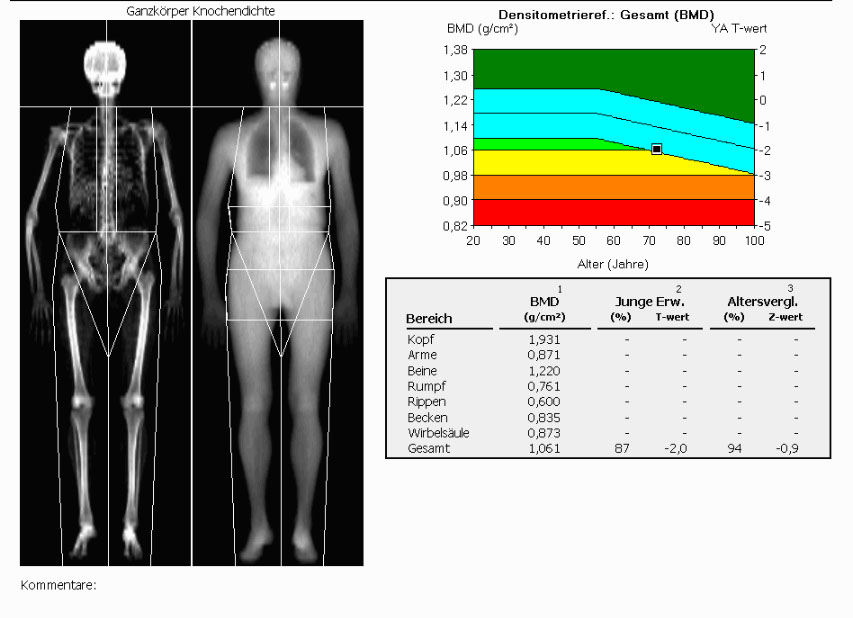

Moderne Geräte zur Knochendichtemessung wie unser Lunar-Prodigy können mehr: Unter anderem ist auch eine Analyse der Körpergewebszusammensetzung und der Körpersymmetrie möglich. Die Bodycomposition Messung dient zur Bestimmung der Muskel- und Fettmasse, wobei die Ganzkörperfettverteilung einen wichtigen Gesundheitsparameter darstellt und Aufschluss über das individuelle Risikoprofil gibt. Das Verhältnis zwischen Muskelmasse und Fett ist ein entscheidender Parameter für den jeweiligen Trainingszustand von Hobby- und Leistungssportlern und bei Kontrolluntersuchungen für Rekonvaleszenz und Trainingsaufbau indiziert. Der Körperfettanteil der Betroffenen kann beispielsweise vor bzw. nach einer Diät, einer Fettabsaugung oder unter regelmäßigem körperlichem Training analysiert werden.

Die Untersuchung kann auch in Kombination mit der Knochendichtemessung erfolgen.